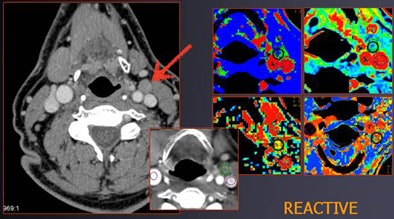

| Patient with oral cancer shows very high values for rBF, rBV, and PS; lymph node was found to be malignant at histology. |